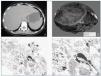

Las pruebas de imagen realizadas (ecografía y TAC abdominal) muestran una imagen de gran tamaño compatible con adenoma hepático en lóbulo hepático derecho (fig. 1a), con riñones de tamaño y ecoestructura normal. Se realiza seguidamente biopsia rectal que demuestra la existencia de depósitos de amiloide de tipo AA en los vasos de la submucosa (técnica de inmunohistoquimia).

Con el diagnóstico de síndrome Nefrótico secundario a amiloidosis en paciente con probable adenoma hepático, se remite al Servicio de Cirugía que programa su ingreso para intervención quirúrgica. En julio de 2003 se realiza hepatectomía parcial derecha (fig. 1b). El diagnóstico de adenoma hepático es confirmado histológicamente, observándose también depósitos de amiloide de tipo AA en el tejido renal, hepático y tumoral (figs. 1c, d).